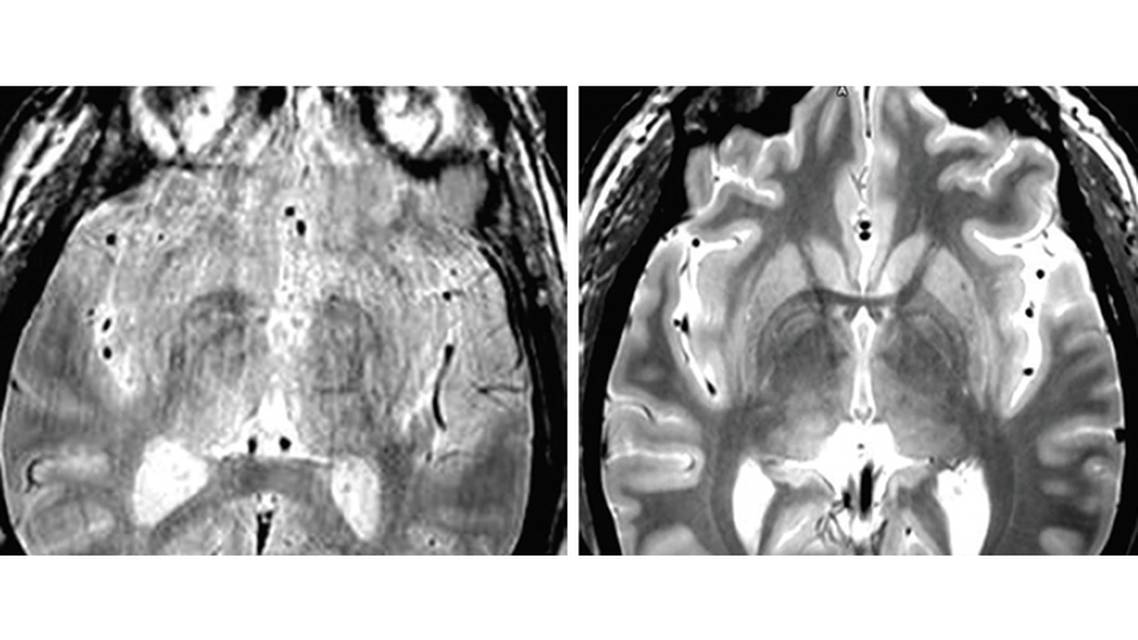

Both brain anatomy and neuroimaging quality are variable, and in order to see exactly where to go in a particular individual’s brain, neuroimaging must be optimized. In our practice, neuroimaging for DBS used to appear as in the Figure; whereas now, after optimization, we see much clearer images, as on the right. To make the change, we had to work with our radiologists and MR physicists to optimize the imaging parameters. Because people being treated for movement disorders can’t help but move in the MRI machine, preventing high-quality image acquisition, we also routinely obtain presurgical imaging with patients under general anesthesia.